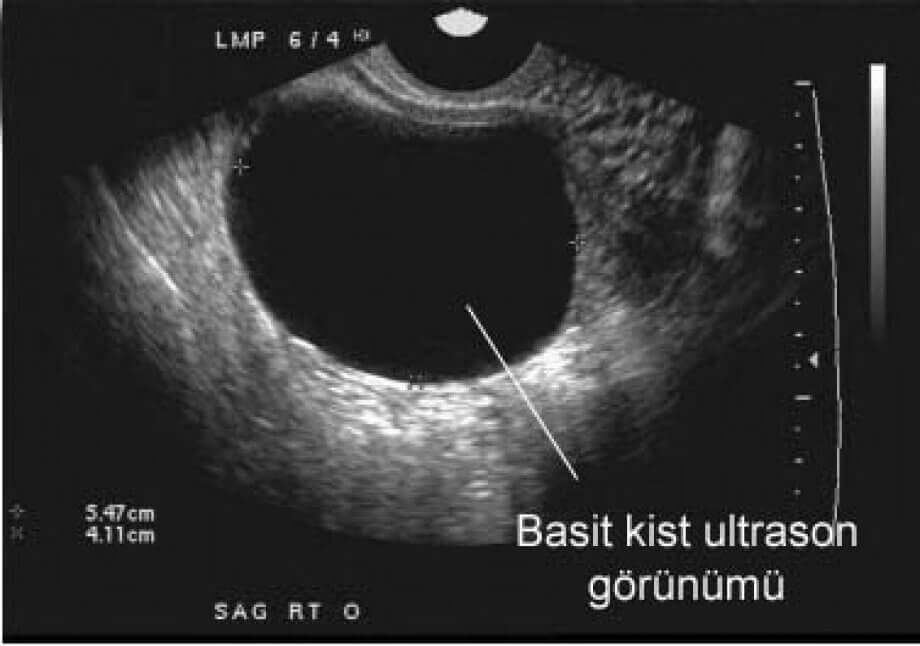

Jinekoloğunuz sizi muayene ederken elle muayene sırasında kistten şüphelenebilir; ancak en kesin tanılar görüntüleme yöntemleri ile koyulur.